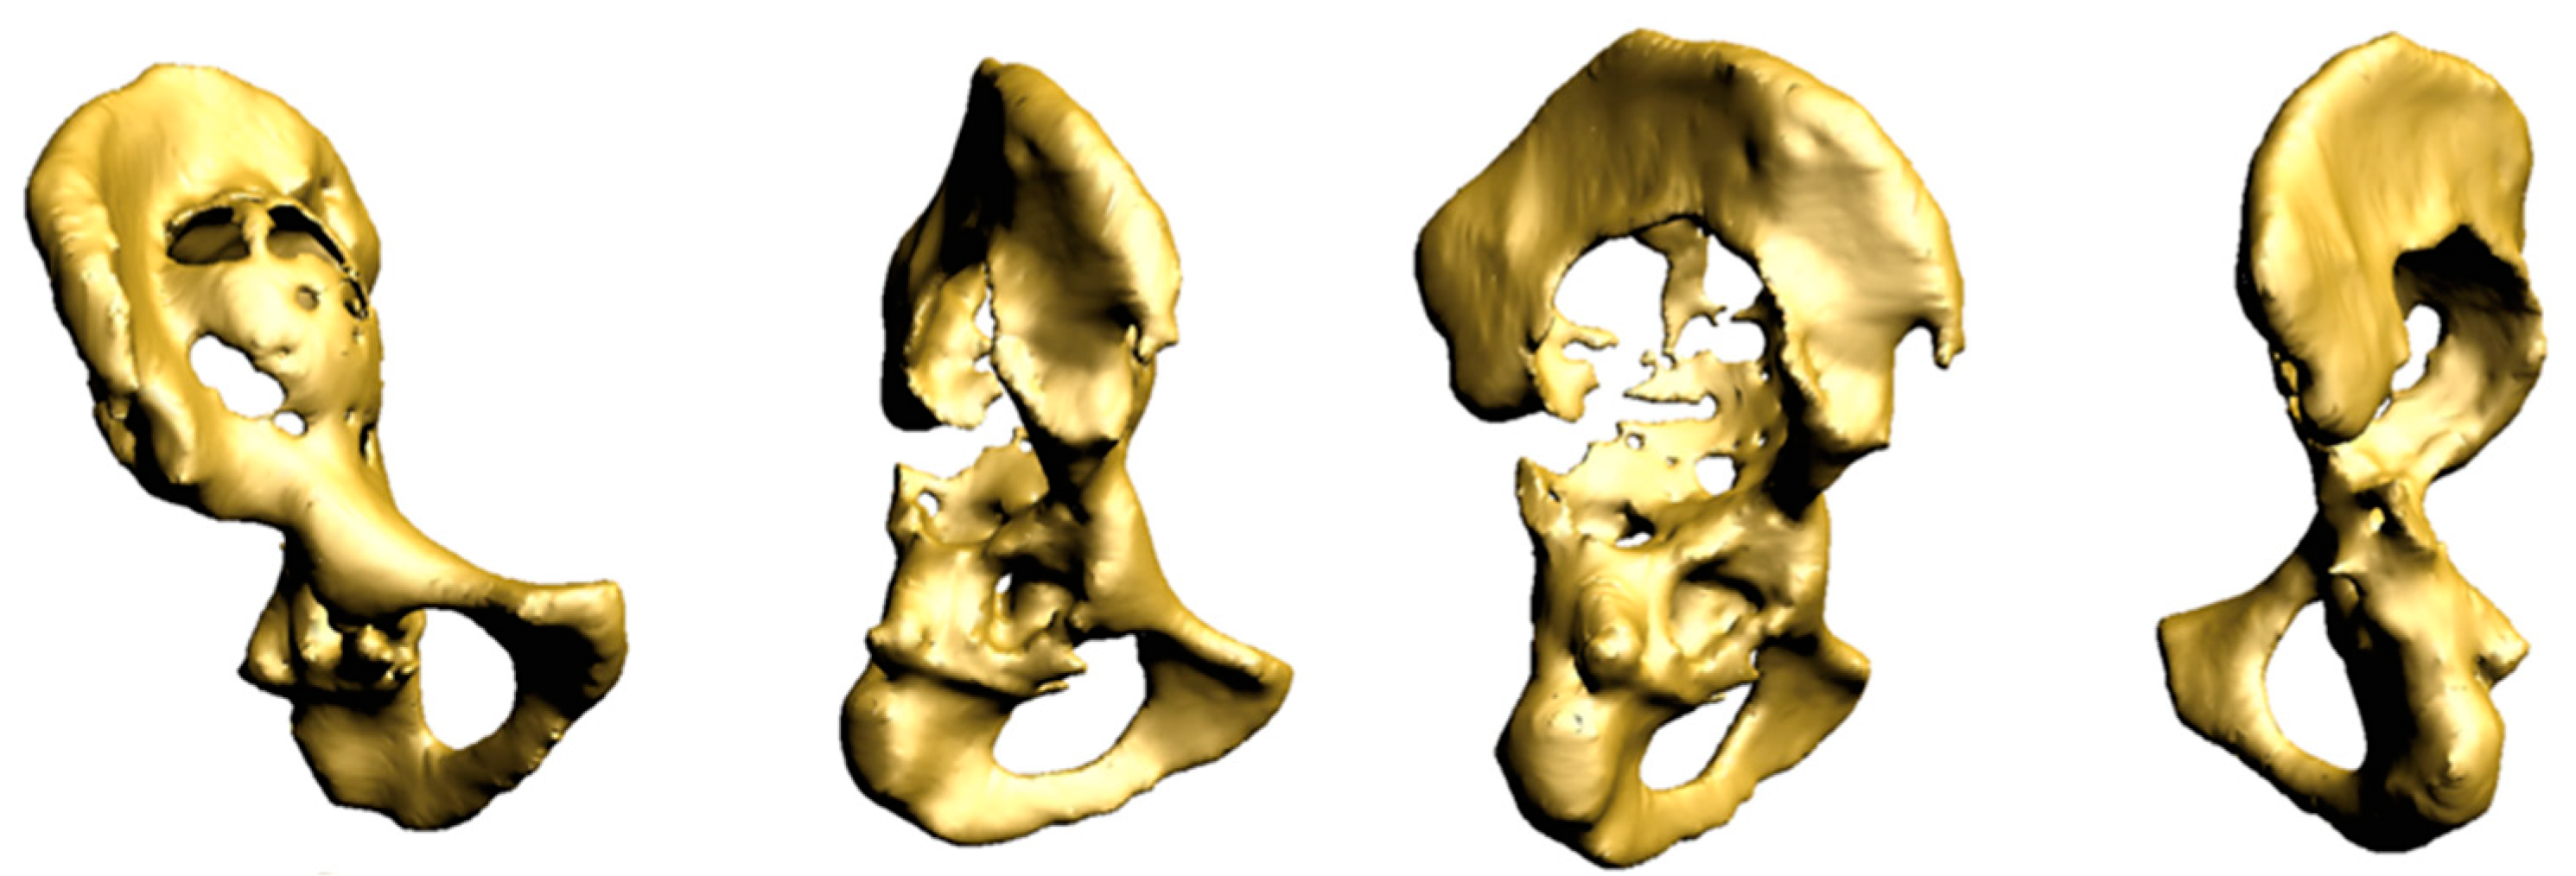

2.1. Case #1

2.2. Case #2